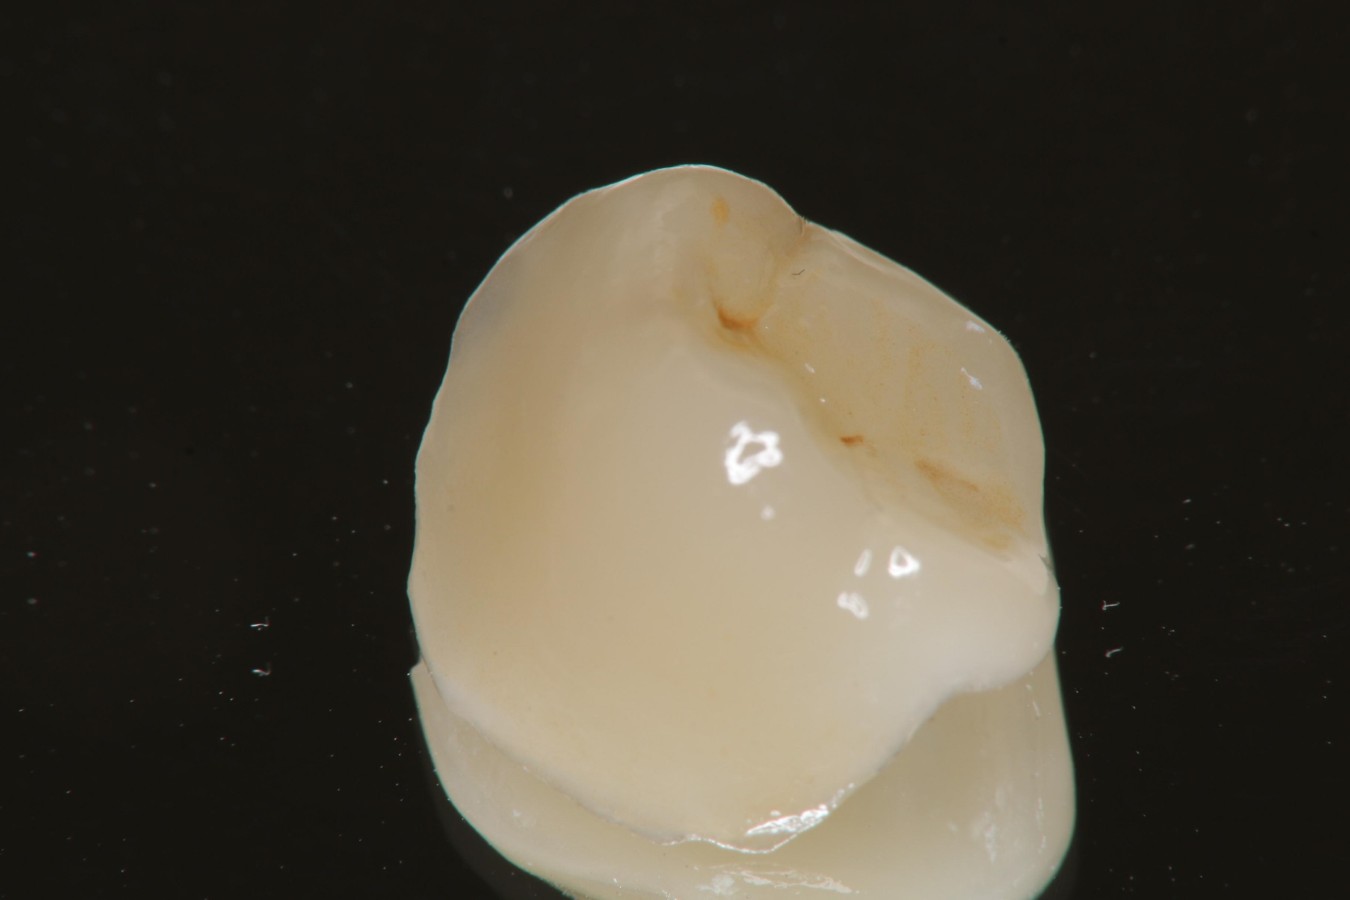

陶瓷冠塊體